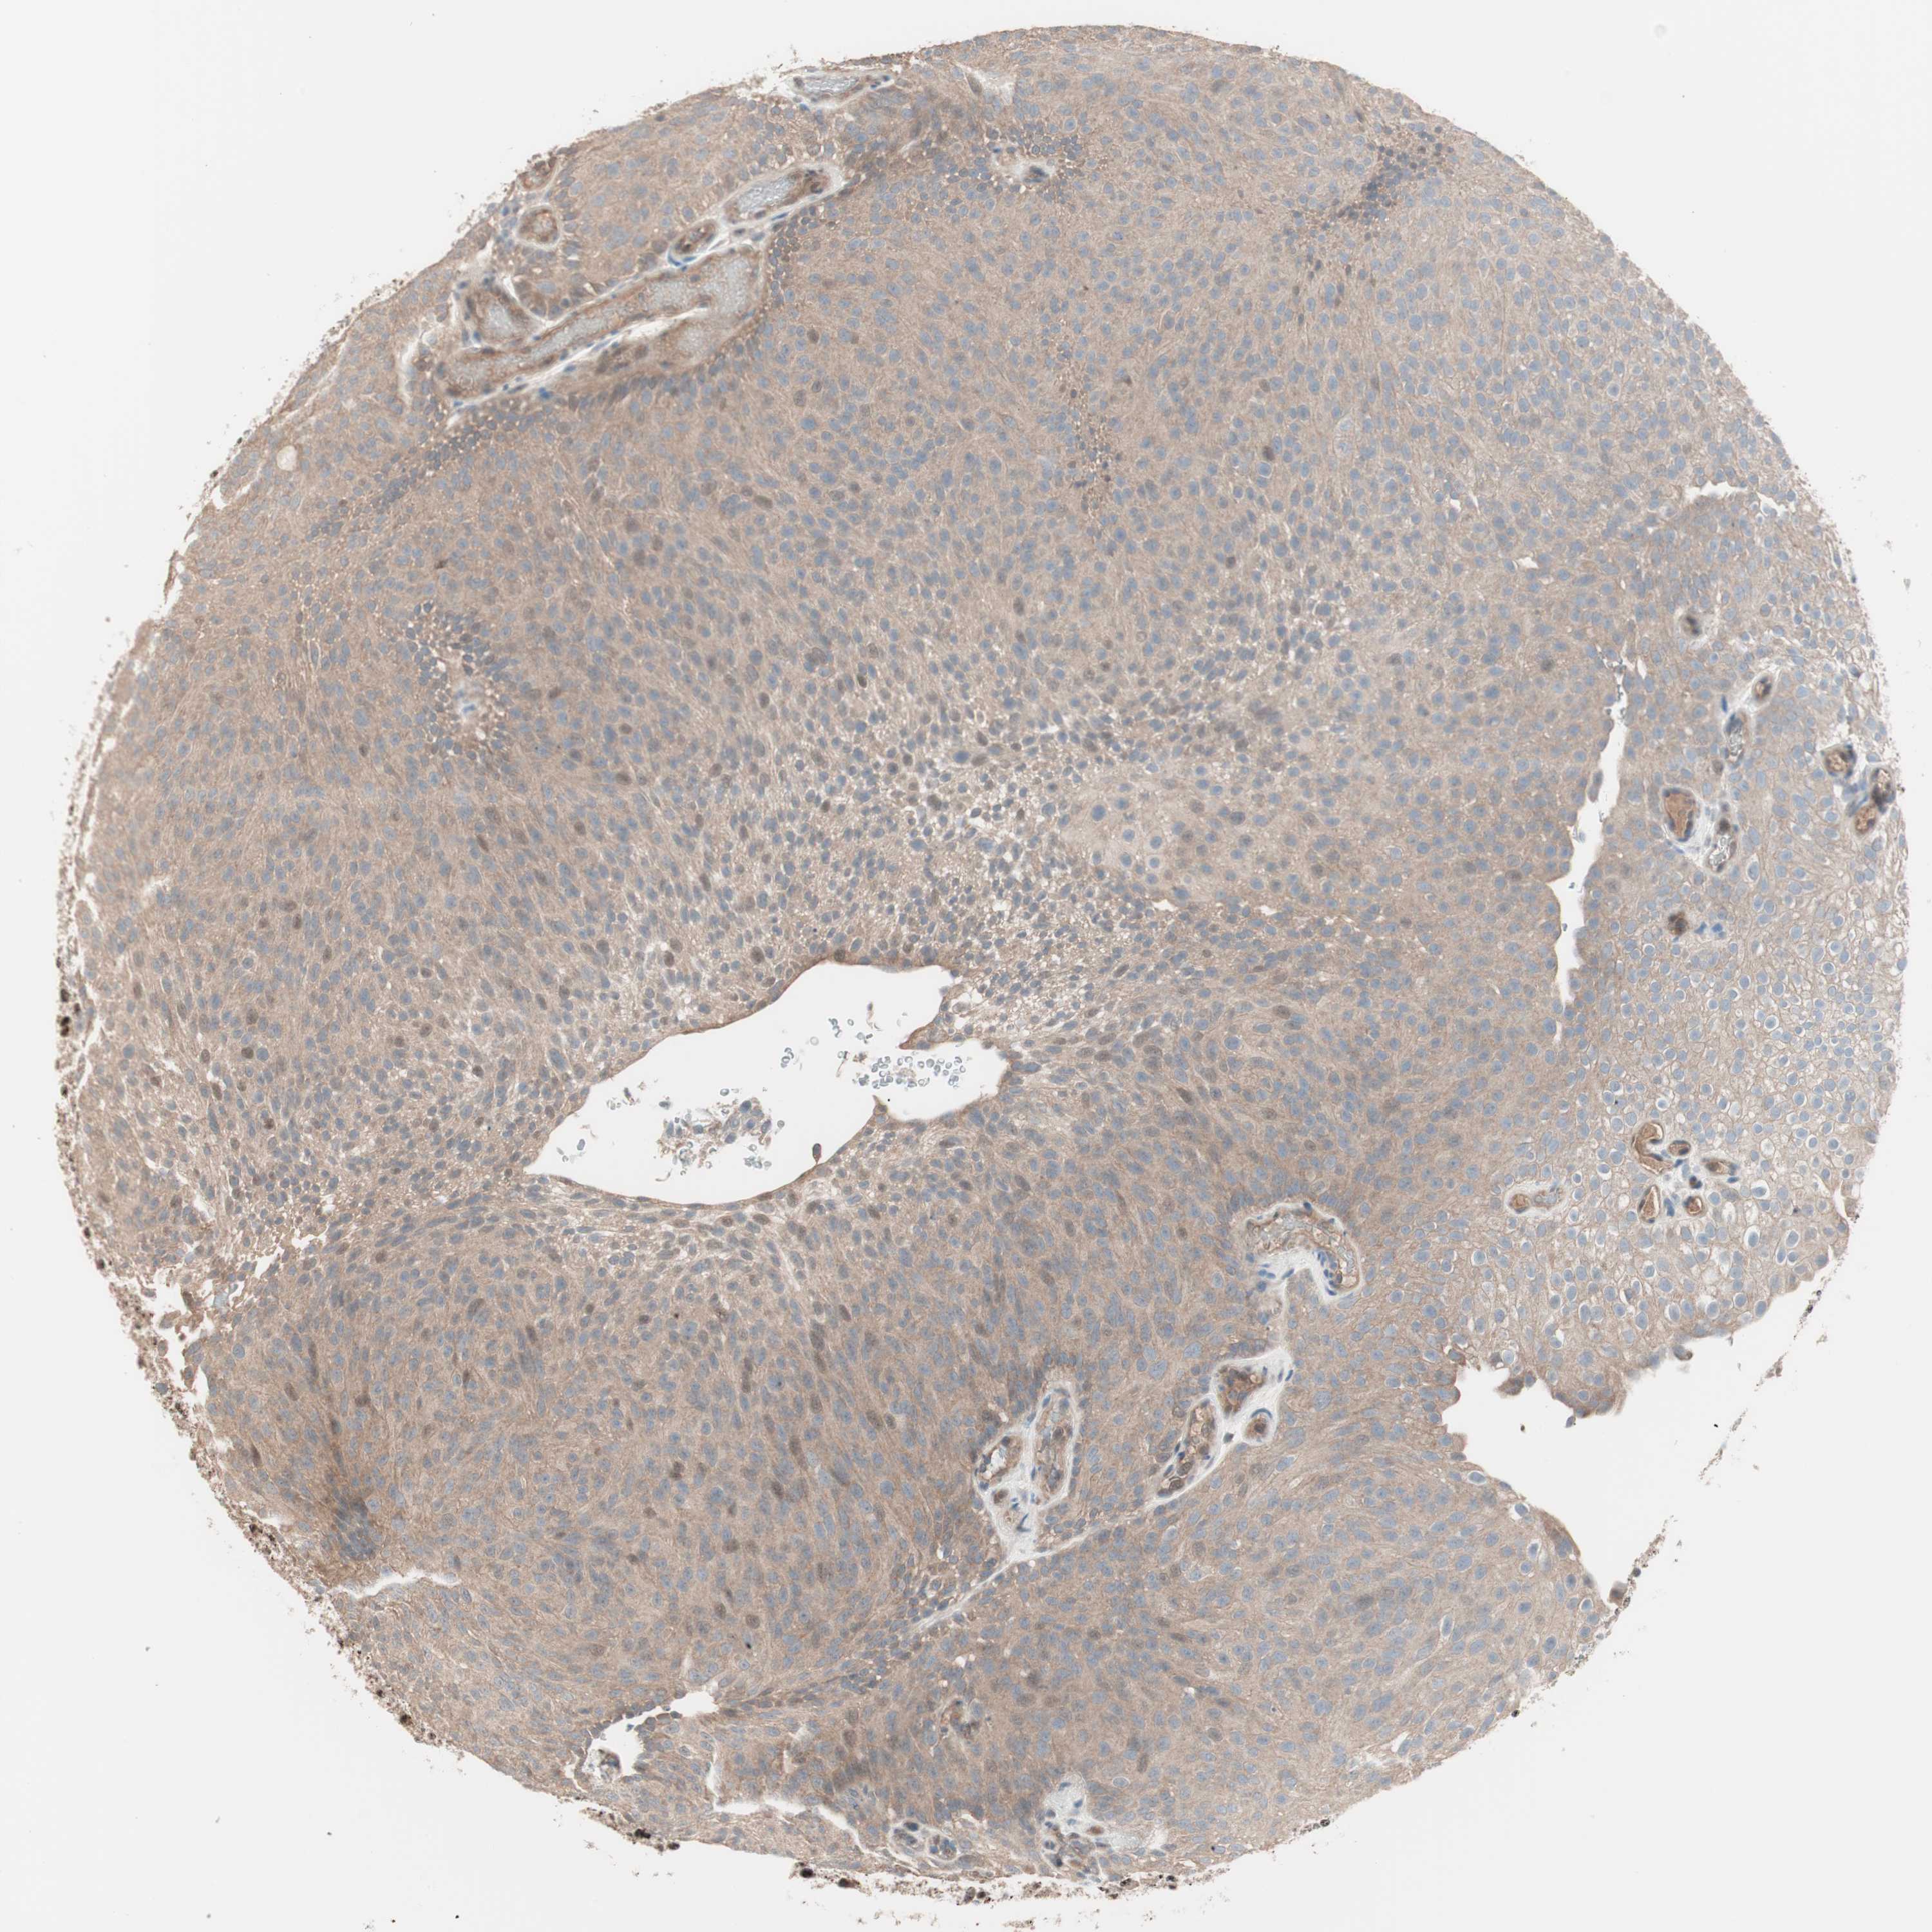

UROTHELIAL CANCER - Protein expressioni

A mouse-over function shows sample information and annotation data. Click on an image to view it in a full screen mode. Samples can be filtered based on level of antibody staining by selecting one or several of the following categories: high, medium, low and not detected. The assay and annotation is described here.

Note that samples used for immunohistochemistry by the Human Protein Atlas do not correspond to samples in the TCGA dataset.

Antibody stainingi

Antibody staining in the annotated cell types in the current human tissue is reported as not detected, low, medium, or high, based on conventional immunohistochemistry profiling in selected tissues. This score is based on the combination of the staining intensity and fraction of stained cells.

Each image is clickable and will lead to virtual microscopy that enables deeper exploration of all samples and also displays staining intensity scores, fraction scores and subcellular localization as well as patient and tissue information for each sample.

Antibody HPA005455

Antibody HPA017067

Urothelial carcinoma, Low grade

Urothelial carcinoma, High grade